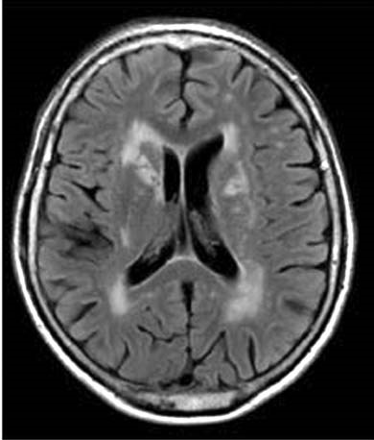

Fazekas grades. Лейкоареоз головного мозга мрт. Перивентрикулярный лейкоареоз мрт. Лейкоареоз Фазекас. Лейкоареоз на кт.

Fazekas grades. Лейкоареоз головного мозга мрт. Перивентрикулярный лейкоареоз мрт. Лейкоареоз Фазекас. Лейкоареоз на кт.

Fazekas grades. Лейкоареоз головного мозга мрт. Перивентрикулярный лейкоареоз мрт. Перивентрикулярный лейкоареоз головного мозга на кт. Лейкоареоз Fazekas 1 что это.

Fazekas grades. Лейкоареоз головного мозга мрт. Перивентрикулярный лейкоареоз мрт. Перивентрикулярный лейкоареоз головного мозга на кт. Лейкоареоз Fazekas 1 что это.

Fazekas grades. Лейкоареоз головного мозга мрт. Лейкоареоз 2 степени по Fazekas. Очаги микроангиопатии в веществе головного мозга Fazekas Grade 1. Лейкоареоз 3 степени по Fazekas.

Fazekas grades. Лейкоареоз головного мозга мрт. Лейкоареоз 2 степени по Fazekas. Очаги микроангиопатии в веществе головного мозга Fazekas Grade 1. Лейкоареоз 3 степени по Fazekas.

Fazekas grades. Лейкоареоз головного мозга мрт. Лейкоареоз на кт. Церебральная микроангиопатия мрт. Перивентрикулярный лейкоареоз мрт.

Fazekas grades. Лейкоареоз головного мозга мрт. Лейкоареоз на кт. Церебральная микроангиопатия мрт. Перивентрикулярный лейкоареоз мрт.

Fazekas grades. Лейкоареоз головного мозга мрт. Перивентрикулярный лейкоареоз на кт. Лейкоареоз Fazekas 2. Лейкоареоз Fazekas 1 что это.

Fazekas grades. Лейкоареоз головного мозга мрт. Перивентрикулярный лейкоареоз на кт. Лейкоареоз Fazekas 2. Лейкоареоз Fazekas 1 что это.